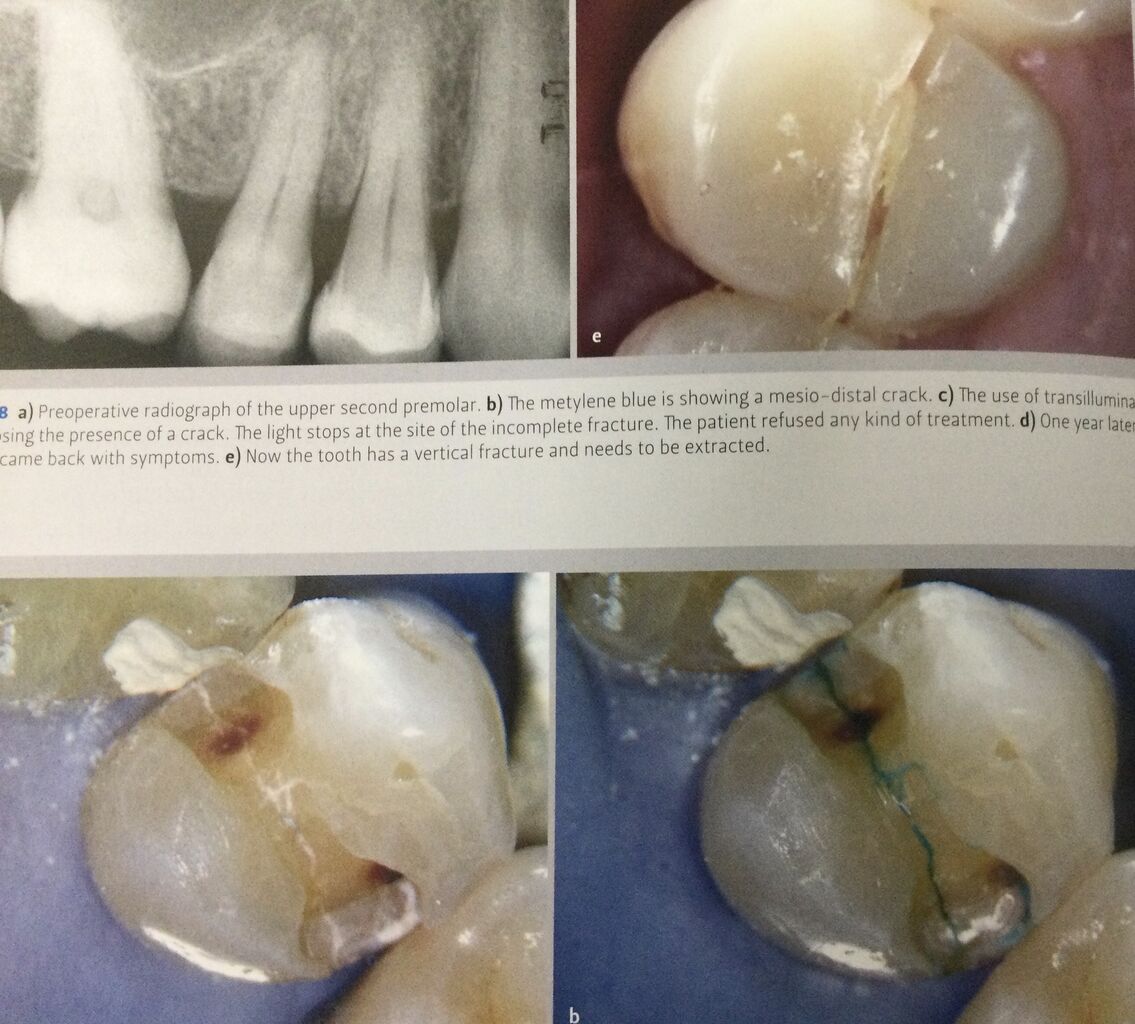

強い光を当てて見る検査も、ヒビを見つけるのに有効です。

ヒビが有ると、ヒビから先には光が届かず暗く見えます。

下の様に染色するとヒビに色が付いて分かります。